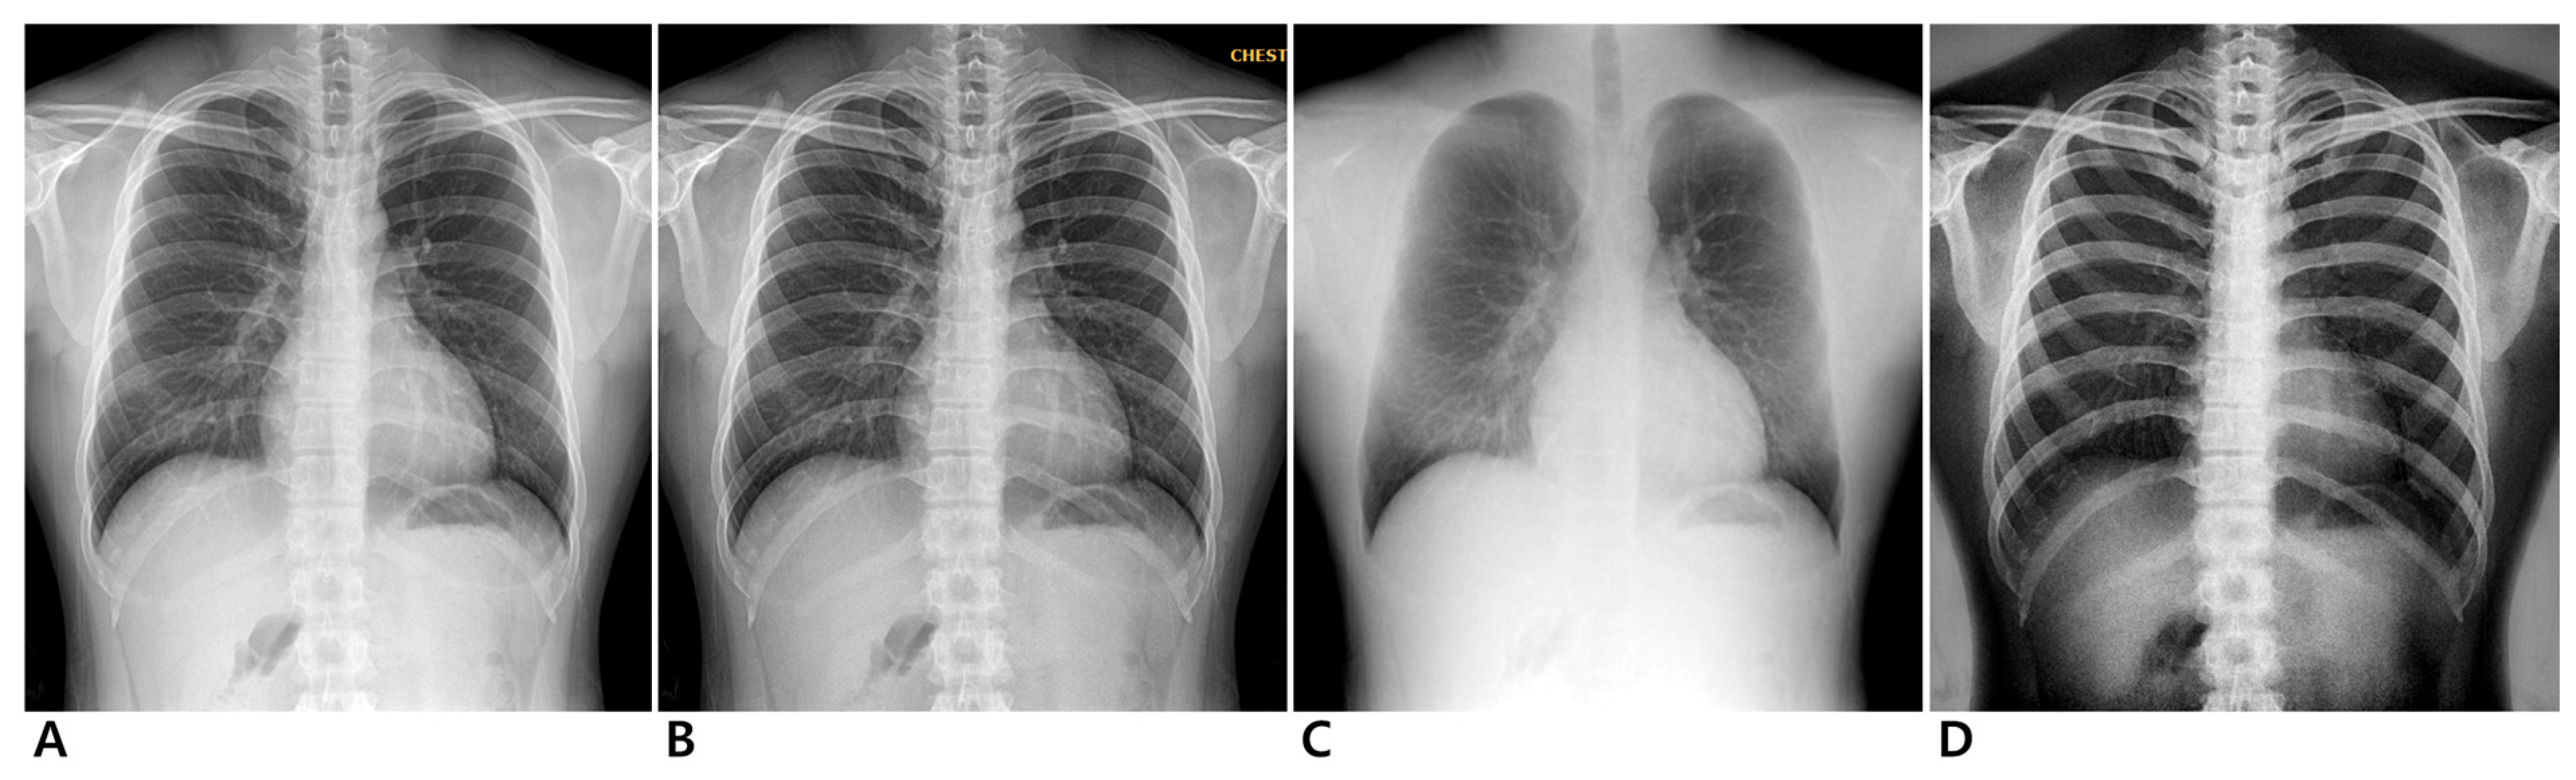

Dual-energy chest radiography was performed with a digital radiographic system (EXSYS PLUS; DRTECH Corp., Seongnam-si, Republic of Korea) equipped with a 430 × 430 mm indium-gallium-zinc oxide (IGZO) thin-film transistor detector, a CsI scintillator, and pixel dimensions of 140 micron pixel pitch. To ensure consistent positioning, all participants underwent a standard PA chest radiograph guided by a radiographer. Before the scan, participants were positioned upright with their anterior chest against the image receptor. They were instructed to place their hands on their hips with elbows slightly forward and to take a deep breath, holding it during the exposure to optimize lung expansion. The X-ray beam was directed perpendicular to the detector at approximately the level of the seventh thoracic vertebra. Images were acquired with two exposures using 60 kVp for the low energy and 120 kVp for the high energy at 150 ms intervals. Fixed tube currents of 250 mA and 200 mA were used for low- and high-energy acquisitions, respectively. To further control for variability due to body habitus, the automatic exposure control system measured X-ray transmission in real time and automatically adjusted the exposure time according to the participant’s body size (Supplemental Table S1). This ensured that all images were acquired under consistent exposure conditions, minimizing variations due to differences in participant body composition. The source-to-image receptor distance was 180 cm, and an anti-scatter grid (215 lines per inch; ratio, 10:1) was installed. The image from the high-energy exposure served as the conventional radiography image. The dual-energy subtraction algorithm generated three images for each participant: an enhanced standard image, a soft-tissue-selective image, and a bone-selective image (Figure 1 and Figure 2). All images were processed with a standardized postprocessing algorithm supplied by the manufacturer (Econsole1 SW; DRTECH Corp., Seongnam, Republic of Korea).

Figure 1.

Chest radiographs of 24-year-old male participant. Conventional (A), enhanced standard (B), soft-tissue-selective (C), and bone-selective (D) images.